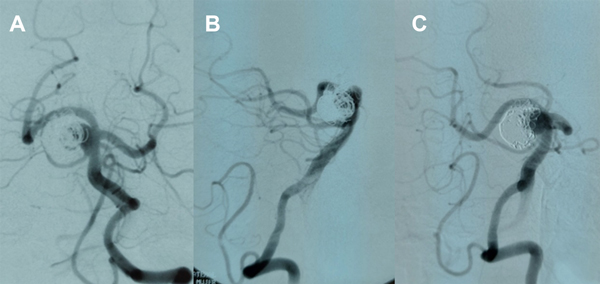

Figura 1. Ejemplos de aneurismas tipo BA (paciente 16, caso 17), tipo BA- SCA (paciente 9, caso 10) y tipo PCA- SCA (paciente 15, caso 16).

En nuestra serie, el resultado inmediato ideal se obtuvo en 8 de 19 pacientes (42%), con 9 remanentes de cuello, y remanente de saco en 1 caso que fue retratado y en control posterior volvió a mostrar permeabilidad (figuras 2-4).

Fig. 2. Paciente 1, caso 1. Año 1994. Control a 2 meses de embolización post hemorragia subaracnoidea, cuello permeable.

Fig. 3. Paciente 1, caso 3. Año 1996. Franca repermeabilización a 3 años (a, b), nueva embolización con coils (c, d).

Fig. 4. Paciente 1. Control año 1999, 3 años posterior al re tratamiento, permeabilidad parcial del cuerpo del aneurisma (Raymond- Roy 3).